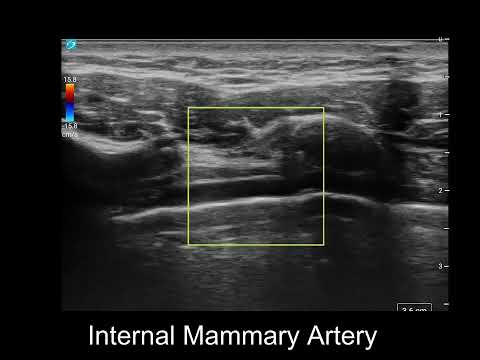

Cardio-vascular, Anesthesiology, ICU, perioperative medicine, POCUS, CHU Dijon, UMR 1231 SFAR, ARCOTHOVA, ESAIC